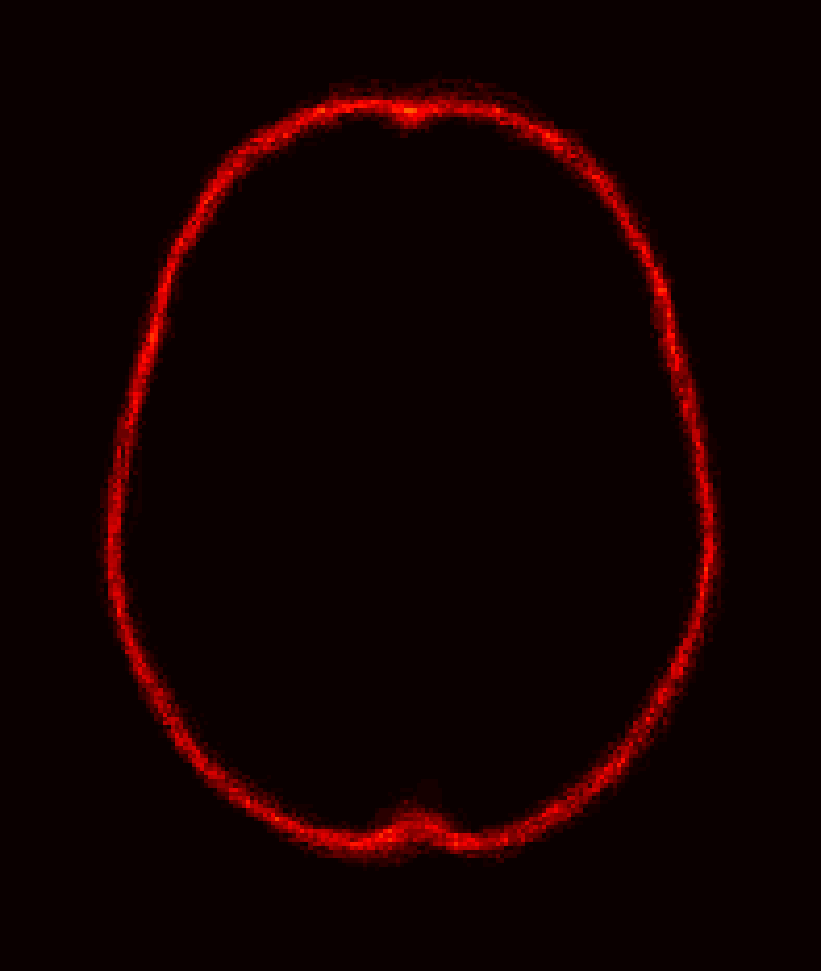

For IBSR, segmentations of the brain images into white matter, gray matter and cerebrospinal fluid (CSF) are provided. While, in principle, the union of the segmentations of white matter, gray matter and CSF should represent the desired brain mask, this is not exactly the case (see Fig. 2). To alleviate this issue for each segmentation, we use morphological closing to fill in remaining gaps and holes inside the brain mask and, in particular, to disconnect the background inside the brain mask from the surrounding image background. The structuring element for closing is a voxel and its 18 neighborhood333The 18-voxel connectivity is also used for other morphological operations in this manuscript.. We then find the connected component for the background and consider its complement the brain mask. Fig. 2 shows the pre-processing result after these refinement steps, compared to the original IBSR segmentation (i.e., the union of white matter, gray matter, and the CSF).

[Uncaptioned image] [Uncaptioned image] [Uncaptioned image]

(a) (b) (c)

Figure 2: Example coronal slice of (a) an IBSR MR brain image, (b) the corresponding original IBSR brain segmentation (i.e., union of white matter, gray matter and CSF) and (c) the refined brain segmentation result.